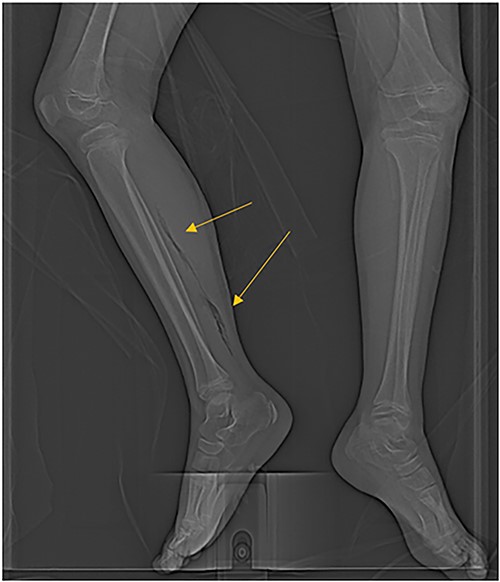

The patient was an 8-year-old female who presented to hospital with a 3-day history of fever, abdominal pain, and coffee ground emesis. On presentation, she was afebrile, tachycardic, and hypotensive. On examination, she had an acute abdomen and septic shock. Initial laboratory investigations revealed a venous pH of 7.08, CO2 of 47 mmHg, bicarbonate of 14 mmol/L, lactate of 3.9 mmol/L, white blood cell count of 3.7 × 109/L with an absolute neutrophil count of 0.96 × 109/L, C-reactive protein of 389 g/L, INR of 1.7, PTT 36 s, fibrinogen of 5 g/L, and an acute kidney injury with a creatinine of 100 micromoles/L and urea of 10 mmol/L. An abdominal ultrasound revealed a starry sky appearance of the liver with moderate free fluid in the right upper quadrant. She was not fluid-responsive and thus was treated with an epinephrine infusion and empiric antimicrobial therapy with ceftriaxone and vancomycin. Transportation was arranged to a tertiary care center with access to pediatric intensive care and surgical services. In transport she developed mild erythema to the right calf with severe pain to palpation and dorsiflexion out of proportion of clinical findings (Fig. 1). Her creatine kinase level was 10 000 U/l and a computerized tomography (CT) scan of the right leg demonstrated extensive soft tissue gas and myonecrosis (Fig. 2). An abdominal CT scan demonstrated evidence of bowel perforation in the right lower quadrant with associated loculation, intra-abdominal free air and fluid, and proximal bowel dilation (Fig. 3). Considering these findings, antibiotics were broadened to piperacillin-tazobactam, vancomycin, and clindamycin, and she was urgently taken to the operating room.

The patient’s right leg upon presentation to the tertiary care hospital, with the area of erythema and edema outlined with a skin marker.